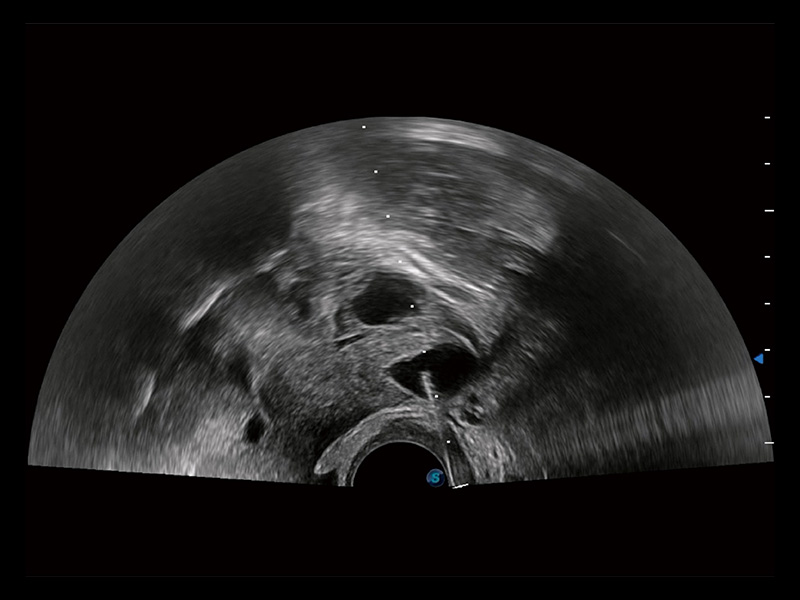

子宫内膜息肉

输卵管间质部妊娠